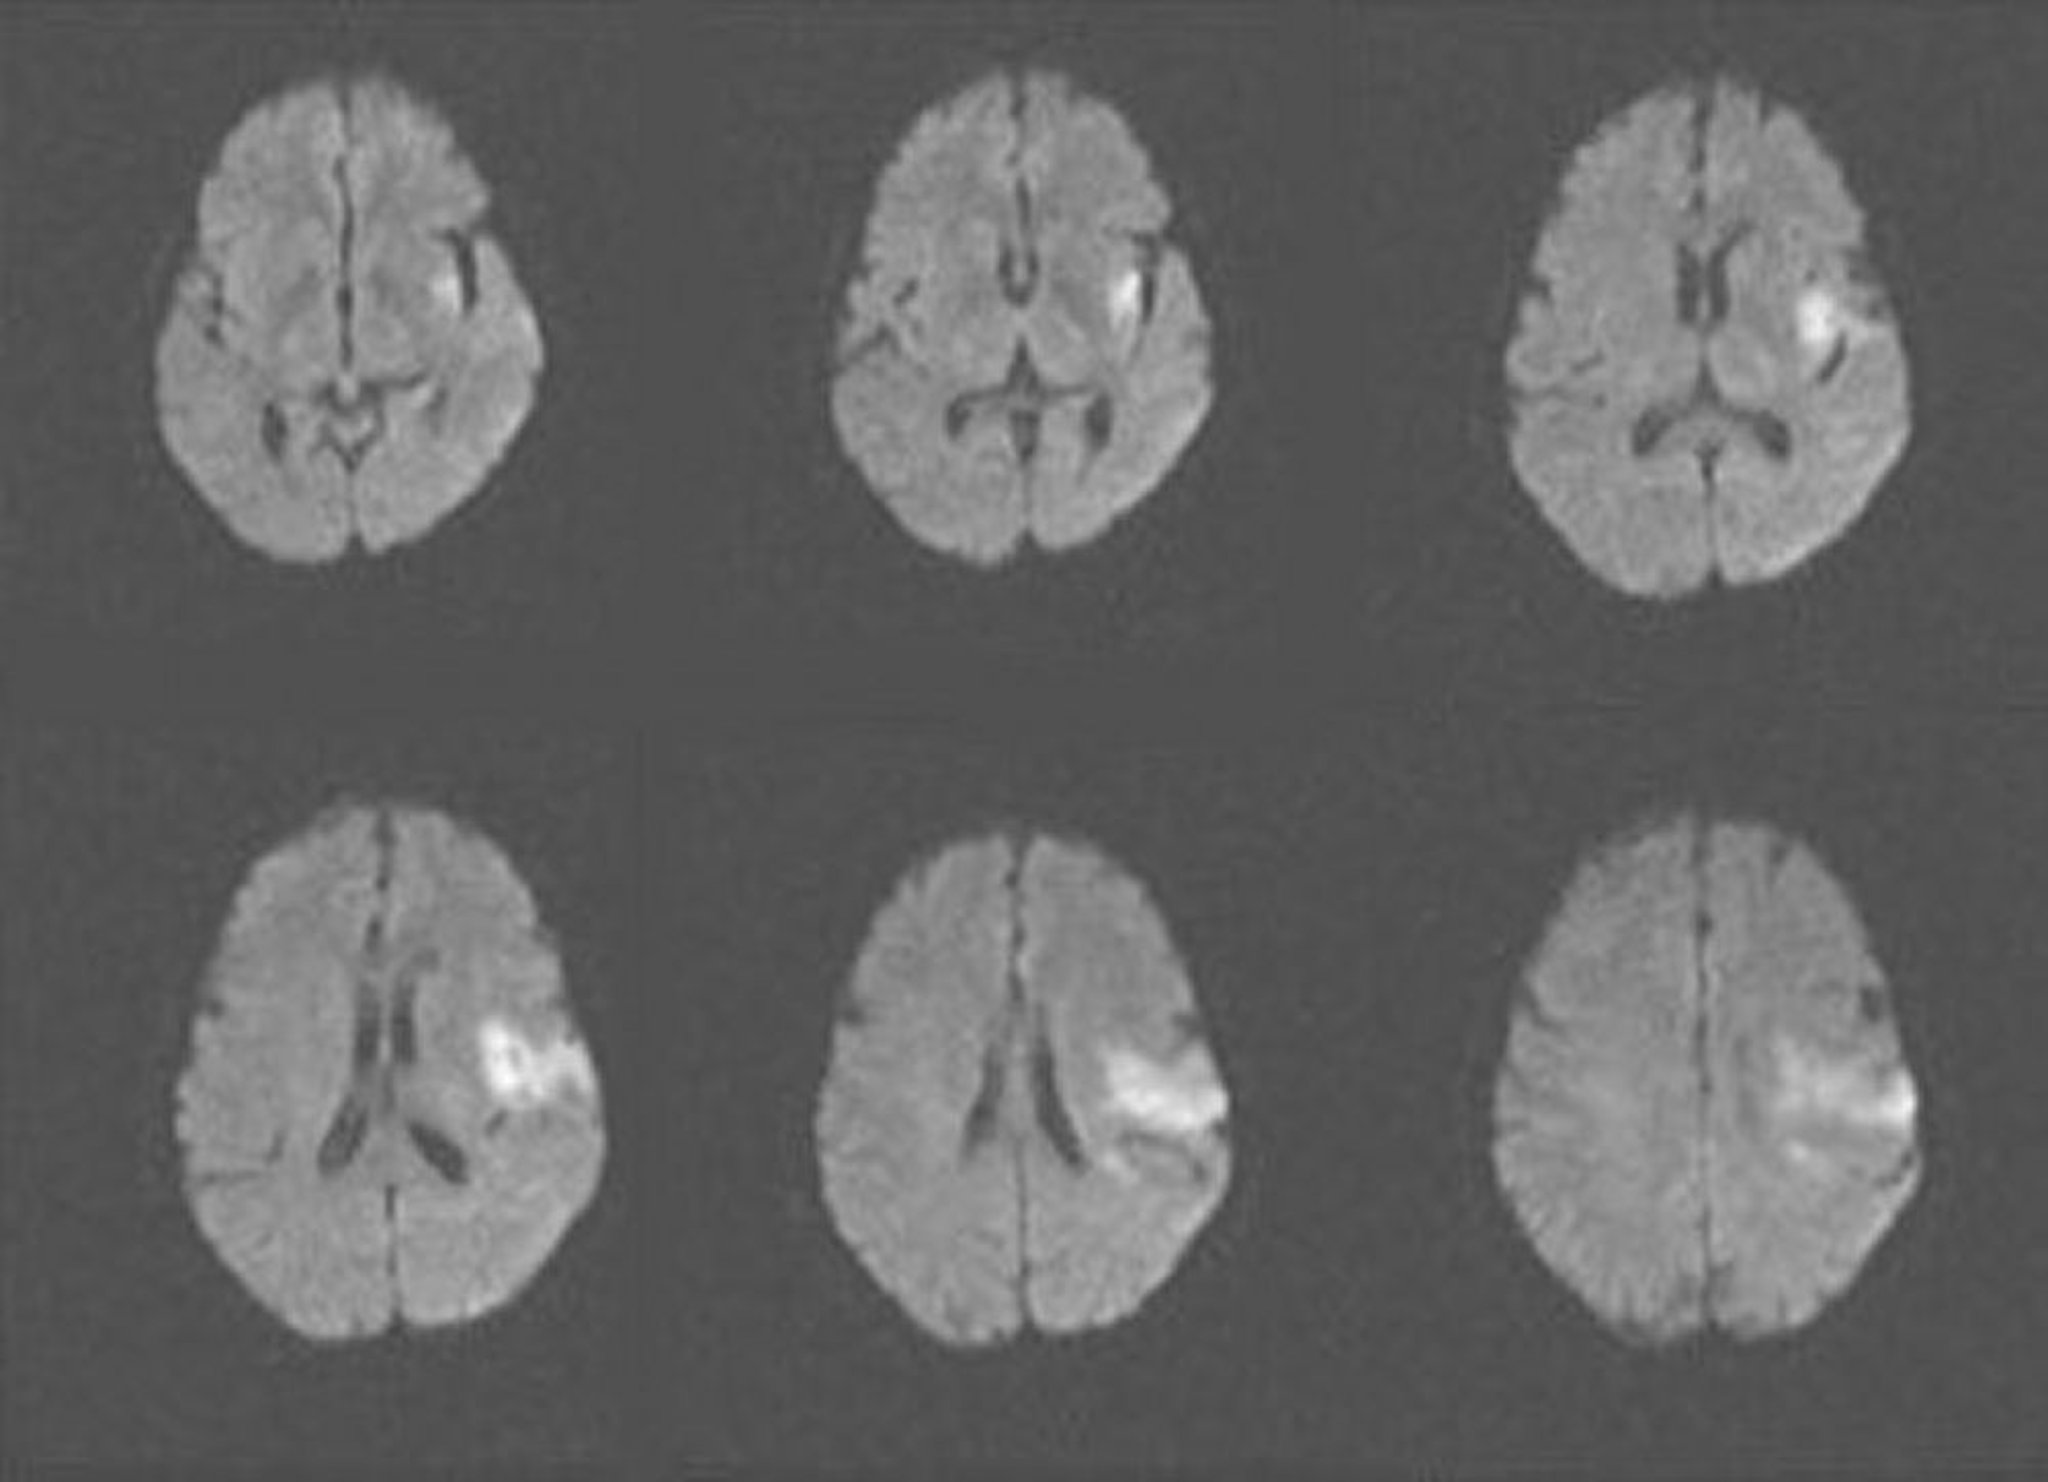

Acute Ischemic Stroke (MRI)

This MRI scan shows an area of restricted diffusion consistent with an acute ischemic stroke in the left insular and frontal lobes.

Image courtesy of Ji Y. Chong, MD.